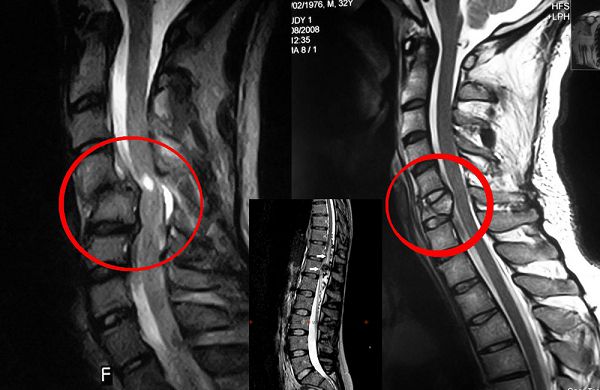

Поскольку симптомы вегетососудистой дистонии (ВСД) и шейного остеохондроза схожи, важной задачей при выборе терапии является точная диагностика и различение этих состояний. Для выявления проблем с позвоночником применяются рентгенография и магнитно-резонансная томография (МРТ). Диагностика ВСД включает электрокардиограмму (ЭКГ), электроэнцефалографию (ЭЭГ) и лабораторные функциональные тесты. Консультация специалистов, таких как кардиолог и эндокринолог, также необходима.